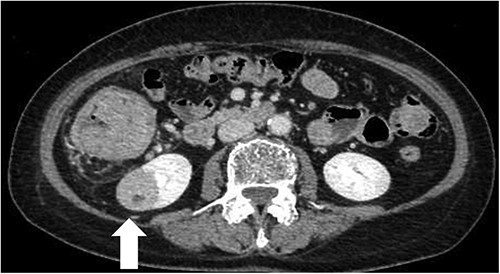

A 68-year-old female patient presented to our hospital with fatigue. She had a history of hypertension and hyperlipidemia. She appeared pale, but a physical examination revealed no other abnormalities. Laboratory findings revealed severe anemia, with a hemoglobin level of 8.8 g/dl. Abdominal computed tomography (CT) revealed tumors in the ascending colon and right lower kidney (Figs 1 and 2). Colonoscopy confirmed a Type 1 tumor in the ascending colon, and biopsies of this lesion revealed papillary adenocarcinoma. Preoperative TNM classification according to UICC classification was colon cancer, stage cT3N0M0, and right renal cancer, stage cT1aN0M0. Because both lesions were indications for robotic surgery, the patient underwent synchronous robotic right hemicolectomy and right partial nephrectomy using the robot da Vinci® Xi. Following the induction of general anesthesia, the patient was placed in the supine position. The first 8-mm trocar was inserted through the umbilicus using the Hasson method. The pneumoperitoneal pressure was maintained at 12 mmHg. Additionally, three 8-mm trocars were inserted under laparoscopic vision in the right lower abdomen, left lower abdomen and upper left abdomen, and a 12-mm trocar for assistance was inserted in the left abdomen (Fig. 3). The table was rotated slightly to the left and 10° head down. The robot was rolled in from the patient’s right side and docked. Robotic Arm 1 was affixed with bipolar forceps, Arm 2 had monopolar scissors and Arm 3 had a cadiere forceps. Starting with the inferior approach, the right ureter, gonadal vessels and Gerota’s fascia were preserved. The duodenum and pancreatic head were spared on the dorsal side, and the mesentery was mobilized.

CT scan of the renal tumor in the lower pole of the right kidney (arrow).